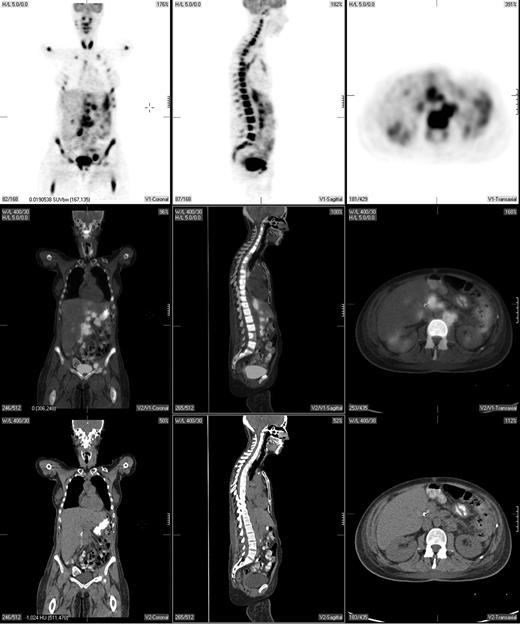

Pretreatment staging determines the extent of disease and helps direct therapy. The Ann Arbor system was initially developed to distinguish patients who might be candidates for radiation therapy from those who would benefit from systemic treatment.29 Traditionally, the Ann Arbor staging system was based on physical examination and bone marrow evaluation but, more recently, CT scans have been incorporated. PET may provide complementary information to conventional staging methods, such as dedicated intravenous contrast-enhanced CT (CECT) and bone marrow biopsy. PET is highly sensitive in detecting nodal and extranodal involvement by most histologic subtypes of lymphoma prior to and following treatment (Figure 1).2,3,20,30-43 Most common types of lymphoma (eg, diffuse large B-cell NHL, follicular NHL, mantle cell NHL, HL) are routinely FDG avid with a sensitivity that exceeds 80% and a specificity of about 90%, which is superior to CT.2,3,33

A pretreatment PET/CT scan in a 48-year-old female patient with Burkitt lymphoma showing widespread nodal and extranodal disease including periaortic, iliac, and mediastinal lymphadenopathy in addition to extensive involvement of the bone/bone marrow, both thyroid lobes and focal liver involvement.